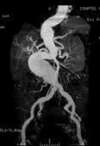

Endoprothèse aortique pour Anévrisme de l'aorte

Depuis 1990, les techniques endo-vasculaires (technique permettant de traiter l’anévrisme sans ouvrir l’abdomen) ont pris le dessus et aujourd’hui il y a plus d’endoprothèse aortique de posées que de chirurgie conventionnelle ne sont réalisées.

Afin de faciliter la mise en place de l’endoprothèse aortique, a été développée depuis plusieurs années de multiples ingéniosités.

Afin de faciliter la pose de celle-ci et en particulier de réaliser le raccordement des deux jambages droit et gauche a été développé un guide aimanté permettant de travailler à l’intérieur de l’anévrisme.

Ces deux guides aimantés l’un vers l’autre vont permettre de se réunir à l’intérieur de la poche anévrismale facilitant ce moment souvent délicat et long.